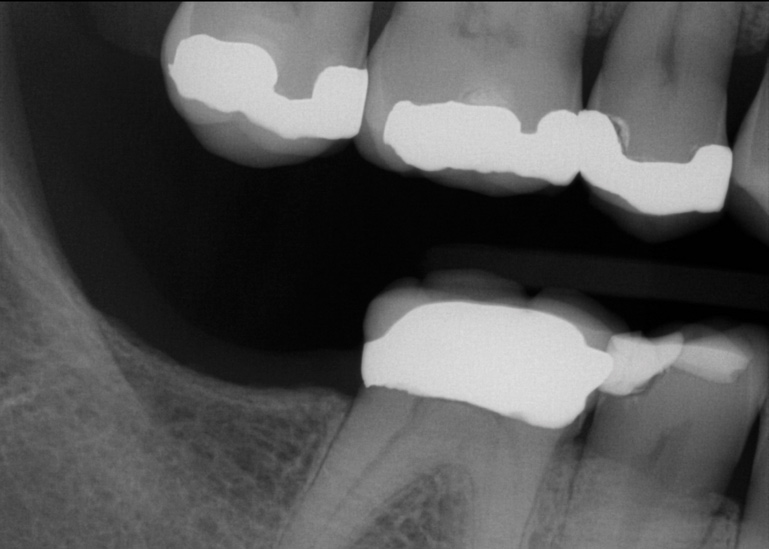

Fig 1. In 2009 patient No. 1 presented with a missing tooth at site No. 31.

Figure 1

Fig 2. In 2016 patient No. 1 manifested no alterations of tooth position No. 2.

Figure 2